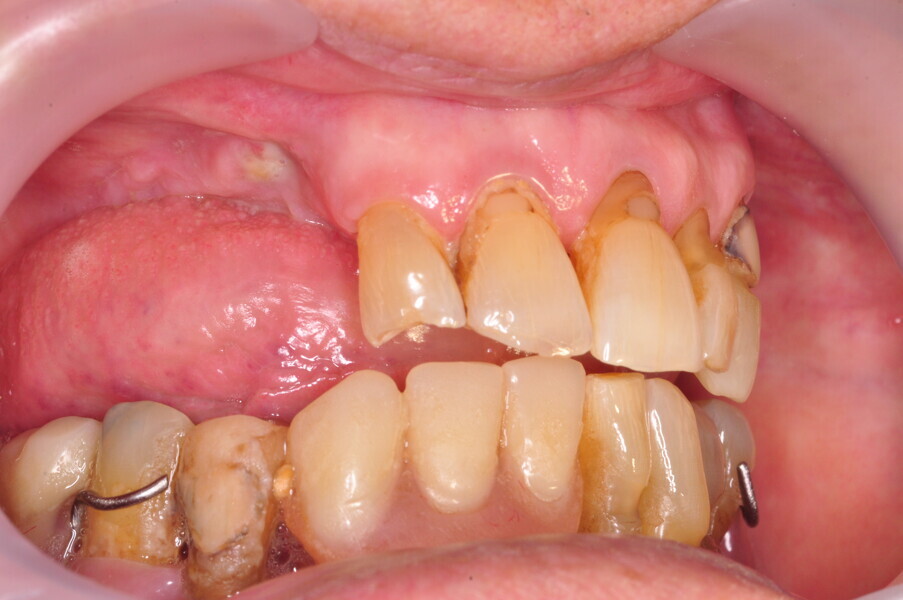

Osteonekroza występująca po zastosowaniu bisfosfonianów